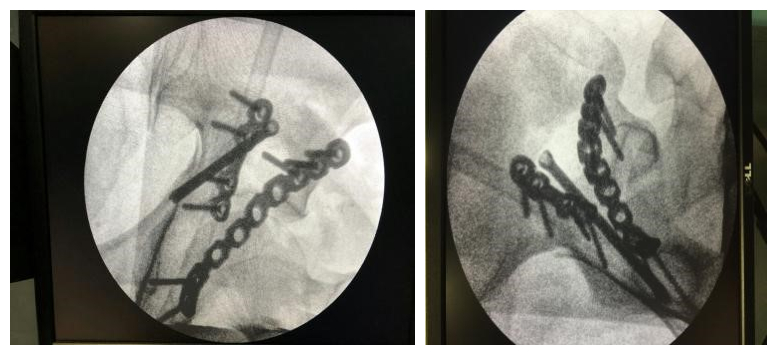

(术中角度验证)

(术中透视固定满意,达预期效果)